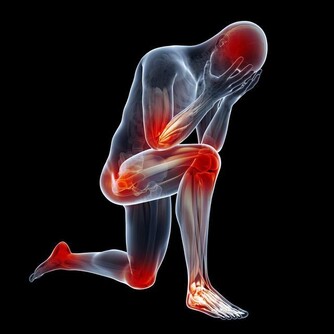

腰椎間盤突出確實常見,腰痛也常見,但是,腰椎間盤突出卻並不是腰痛的主要原因。事實上,腰痛患者符合腰椎間盤突出症診斷標準的比例只有3%~8%。 那麼,大多數人的腰痛是什麼原因引起的呢?該怎麼治療,或者有沒有什麼方法預防呢? 錯誤姿勢是罪魁禍首 我們先來看看腰痛的原因。 日常生活和工作中最容易導致腰痛的原因是彎腰抬物,如工人搬運重物、婦女端放洗衣盆等。在這些情況中,如果不注意姿勢,尤其是平日難得有機會進行重體力勞動的腦力勞動者,或缺乏鍛煉的家庭婦女,很容易造成腰痛。

彎腰抬物如何造成腰痛呢? 通常我們拾取地面重物最常用的方法是直膝彎腰,因為這麼做重心上下移動距離最小,人體消耗能量也最小。 但要注意,這種姿勢雖然做功較少,但是基本上都要靠腰背肌肉發力,腰背肌肉韌帶負擔是較大的,容易造成腰骶部肌肉、韌帶損傷。久而久之,腰背部相對薄弱的肌肉和韌帶就會造成損傷,出現疼痛。 所以說,腰痛的主要病理因素不在腰椎間盤,而在腰背肌肉和韌帶的損傷。三個動作,趕走腰痛! 1.橋式運動 採取仰臥位,雙膝屈曲併攏置於床上,抬起臀部,頭部和肩部置於床面整個人形成拱橋狀故得名橋式運動。